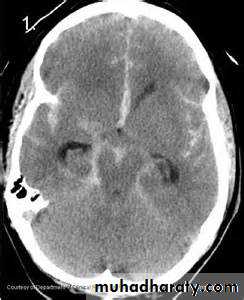

subarachnoid hemorrhage (SAH)

extravasations of blood into the subarachnoid space between the pial and arachnoid membranes80% are due to a ruptured berry aneurysm

Non contrast CT followed by CT angiography (CTA) of the brain can rule out SAH with greater than 99% sensitivity.